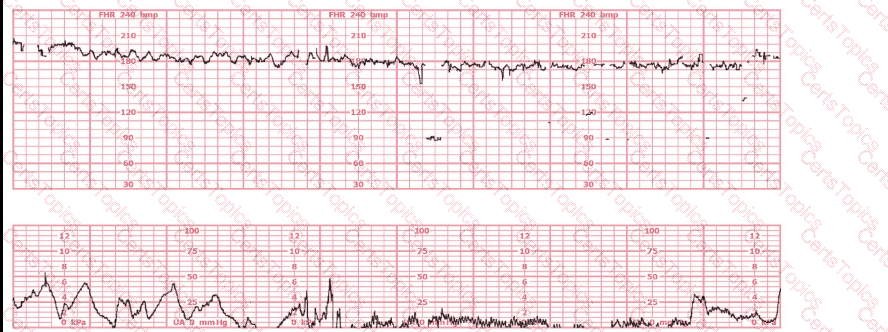

This fetal heart rate tracing is of a woman in labor with dichorionic-diamniotic twins at 36-weeks gestation, 4 cm dilated. She is on oxygen via face mask. Based on the fetal heart rate tracing, what is the most appropriate action?

(Tracing A = black; Tracing B = blue)

The black pattern represents the heart rate pattern for Baby A. The blue pattern represents the heart rate pattern for Baby B. A possible etiology of the baseline fetal heart rate of Baby A is: